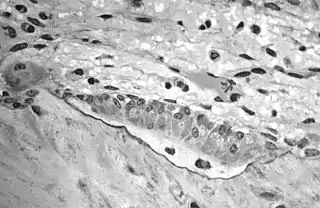

Light micrograph of an osteoclast displaying typical distinguishing characteristics: a large cell with multiple nuclei and a "foamy" cytosol.

Light micrograph of osteoblasts, several displaying a prominent Golgi apparatus, actively synthesizing osteoid containing two osteocytes.